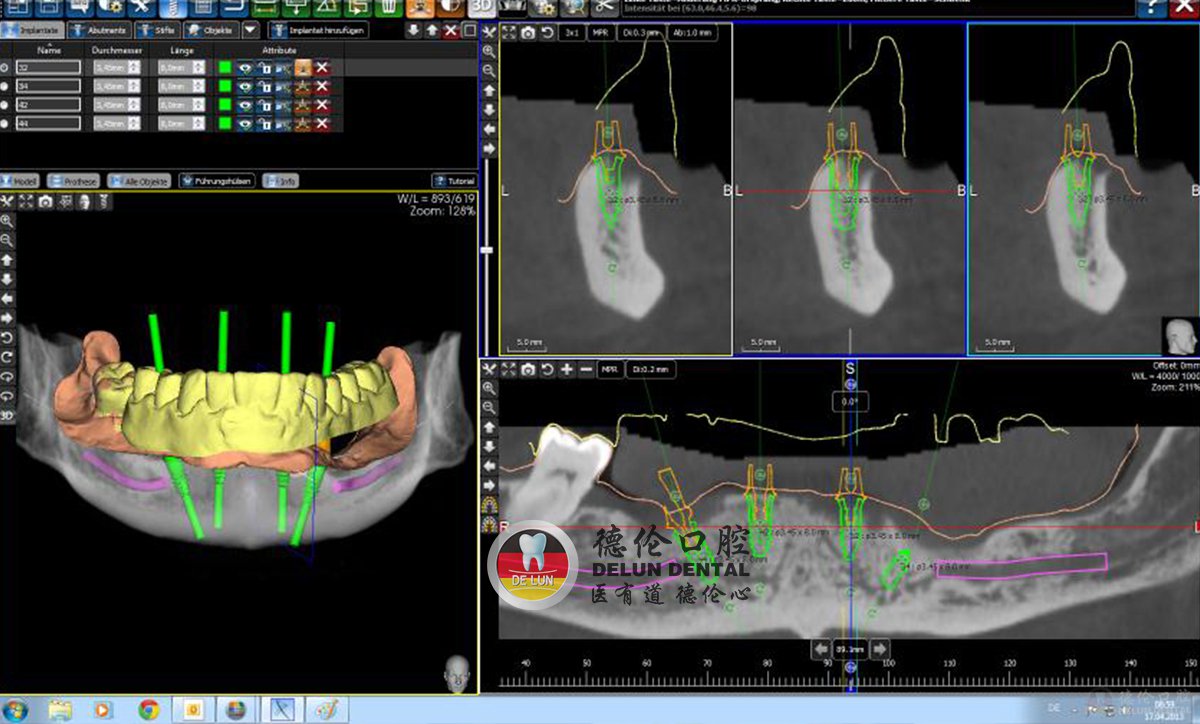

图为:预先在电脑上模拟整个种植过程,确保种植位置的精确

德伦口腔3D导板数字化种植牙技术是在成立国内早一批一站式数字化+技术中心之后,引进全球新型一代德国ICX数字化导板种植系统;对于方案复杂、种植体植入数目较多、手术难度大的无牙颌种植运用有着明显的优势。

优势:大大缩短种植手术耗时,减少创伤,降低手术难度,同时提高种植手术的准确性和可靠性。